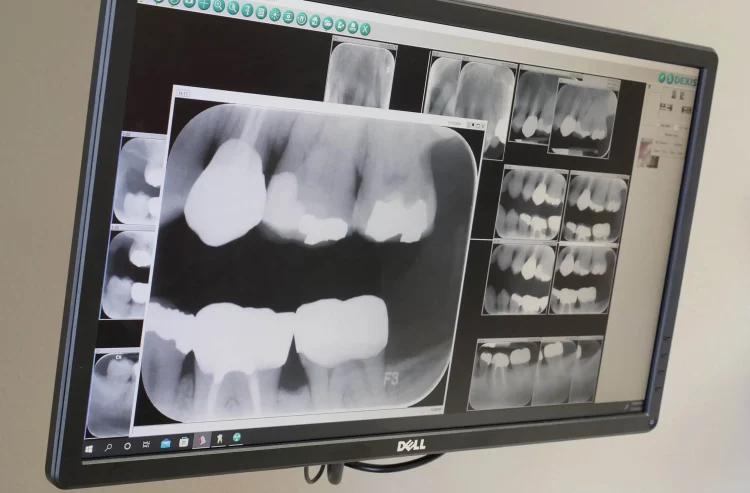

Digital X-rays provide near-instantaneous results. In traditional X-ray methods, the film needs to be developed in a darkroom, which can take several minutes. With digital X-rays, images are captured digitally and can be displayed on a monitor in seconds. This enables both the patient and the dentist to view the image almost immediately, facilitating faster diagnosis and treatment planning.

Moreover, digital X-rays allow for image enhancement. The software used in digital radiography enables dentists to adjust the contrast, zoom in on specific areas, and analyze the image in greater detail. This ability to manipulate the image can help in detecting even the smallest of cavities that might otherwise go unnoticed in a traditional X-ray. By enhancing the image, dentists can better evaluate the health of the teeth, gums, and surrounding bone structures, leading to a more thorough and accurate diagnosis.

3. Improved Image Quality

Digital X-rays offer a superior level of image quality compared to traditional X-ray films. The digital sensors used in these systems capture more detailed images and produce clearer, sharper results. This improved resolution enables dentists to identify cavities at earlier stages of development. Cavities that are still small and may not have been visible with traditional X-ray methods can be detected, allowing for early intervention and treatment. Early detection is crucial because it helps to prevent cavities from progressing to more severe stages, which can require more invasive and costly treatments.